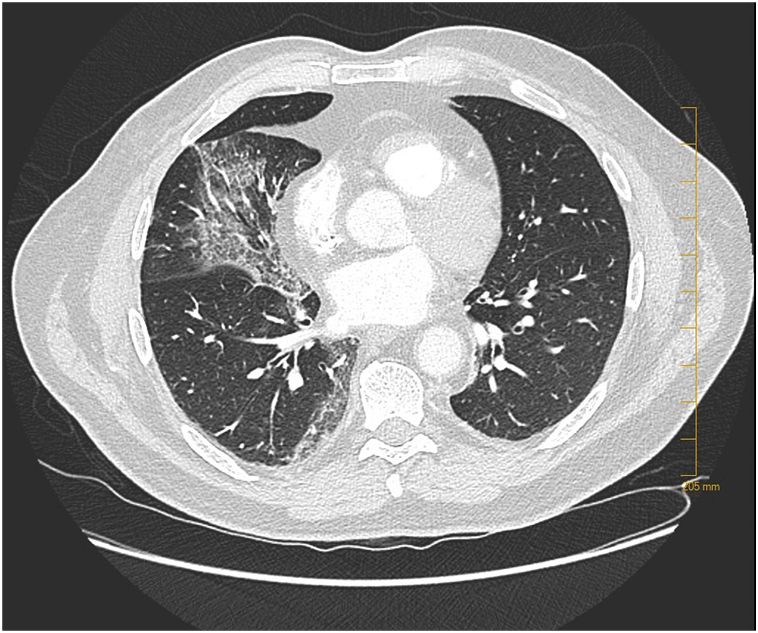

A 63-year-old male was hospitalized and diagnosed COVID-19 two days (day 2) after the beginning of an influenza-like symptoms including cough, myalgia, nausea and headache. His medical history was prostatic neoplasia treated by surgery, active smoking (half a pack of cigarettes a day), and obstructive sleep apnea. At day 4, he was transferred to the infectious disease department of the University Hospital of Clermont-Ferrand because of his dyspnea requiring 1 L/min of nasal oxygen. He received systemic Plaquenil and Azithromycin. At day 7, he was admitted in ICU to manage an acute respiratory syndrome, requiring an invasive ventilation (6 L/min). Chest scanner showed interstitial pneumonia with “crazy paving” patterns (Fig. 1). Daily, analyses of bronchial secretions identified SARS-CoV-2 by Polymerase Chain Reaction (PCR). During the two first weeks of SARS-CoV-2 infection, there were no ocular complaints. At day 17, the first ocular manifestations occurred with conjunctival hyperemia and clear secretions, evoking a viral conjunctivitis. Conjunctival scrapings and swabs did not identify any bacterial (such as Chlamydia, Streptococcus or Staphylococcus) or viral etiology (such as Herpes virus or adenovirus) by direct microscopic examination and culture. The conjunctivitis was treated with eyelid hygiene, eyewash with physiologic serum and artificial tears. At day 19, the clinical signs were exacerbated with follicles, petechias, tarsal hemorrhages, and chemosis (Fig. 2). We identified thin yellowish-white translucid membranes on the tarsal conjunctiva of lower lids that could be easily peeled off without bleeding that we identified as pseudomembranous. The eyelids were irritated by numerous sticky secretions accumulating around the eyelashes. With a fluorescein eyedrop and blue light examination, we described mucous filaments, tarsal pseudomembranous and superficial punctuate keratitis. Because of its intubation, slit lamp and other evaluations of anterior segment complications (such as uveitis or intraocular hypertension) were not performed. The examination of the posterior segment (fundus examination) was completed at patient's bed with the Schepens ophthalmoscope, and did not identify any vitreous inflammation or retinal abnormalities. At day 20, repetition of conjunctival scrapings and swabs did not identify SARS-CoV-2 by PCR in conjunctival secretions and tears. Azithromycin eyedrop was introduced twice a day for 3 days, with low doses of dexamethasone and daily debridement of pseudomembranous to avoid conjunctival fibrosis and retraction. From day 21 to day 26, the ocular symptoms and conjunctivitis decreased, without corneal complications. At the time of writing, the patient is always in intensive care unit.

Fig. 1.

Chest scan of the COVID-19 patient hospitalized in intensive care unit, showing interstitial pneumonia with “crazy paving” patterns.